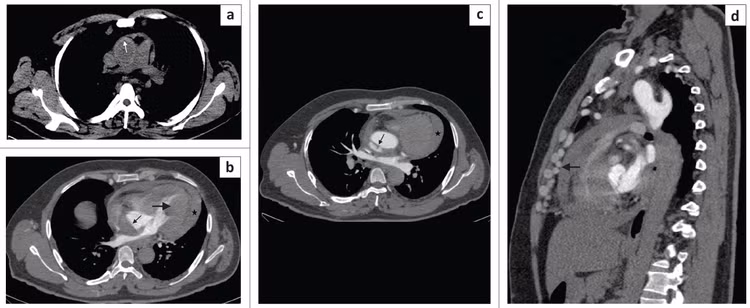

![]() |

| Kết quả chụp CT cho thấy bệnh nhân bị vỡ phình động mạch chủ. Ảnh BSCC |